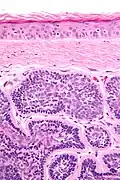

Dermal cylindromas are:

- Dermal lesions consisting of nests of cells that are surrounded by hyaline (i.e., glassy, eosinophilic, acellular) material and have:

- Hyperchromatic nuclei that may palisade (columnar nuclei arranged around the periphery of the cell nests with their short axis tangential to the nest periphery), and

- Cells with lighter staining ovoid nuclei at their centre.

They lack of a significant number of lymphocytes; this differentiates them from spiradenomas.

Micrograph of dermal cylindroma in H&E stain. -